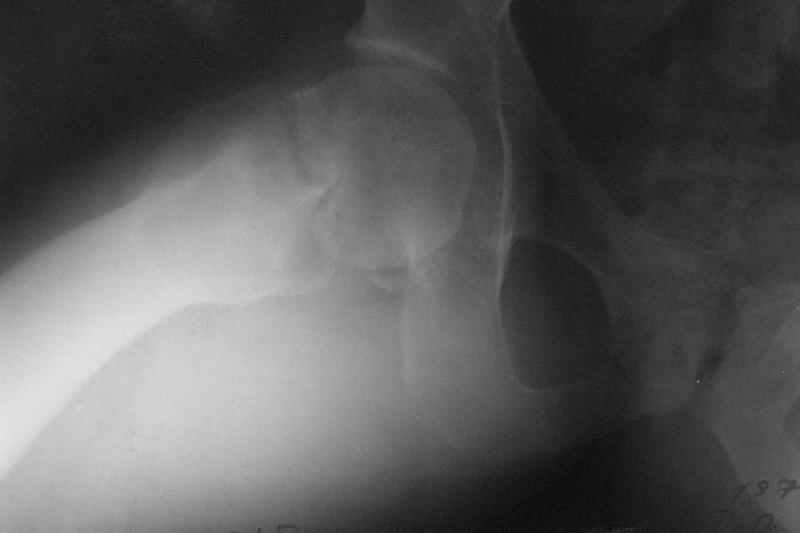

Глубокоуважаемые коллеги,Вчера обратился мужчина 31 г. Травма 2 месяца назад, лечился в одном из городов области. Был не самый тяжелый перелом таза, который проведен консервативно. С ним и связывали невозможность поднять ногу.

Однако на сегодняшнем снимке обнаружился перелом шейки бедра. Больной уже ходитс частичной нагрузкой. Учитывая срок и картину на снимке, что предпринять? У нас предложены варианты 1)не оперировать, 2)закрыто 2 спонгиозных винта, 3)вальгизирующая остеотомия. Эндопротез как-то даже в список включать пока не хочется. Какие есть соображения? Что из перечисленного или что-то другое выбрать и почему? Заранее спасибо.

Dear colleagues,A male 31 years old treated elsewhere after not severe pelvic fracture, was managed non operatively. So the injury looked as a reason of his inability to elevate the leg. However at the recent x-rays the neck fractire was found. The patient already has been walking with partial weight-bearing.Looking at the x-rays and the time since the injury, what is the optimal treatment for now? We discussed 1)leave as is, 2)2 cancellows screws as is, 3)valgus osteotomy. Total hip replacement looks unnecessary yet.What is your opinion? Which option from the listed or something else should be preferred and why?THX in advance.

Варус тут за счет сдвига дистального отломка проксимально. Край шейки на периферическом отломке виден ведь хорошо.

Так его видно на фасном снимке.

Градусов на 25 больше.

Да как же нет, если головка сползла на 2 см дистальнее и кзади.